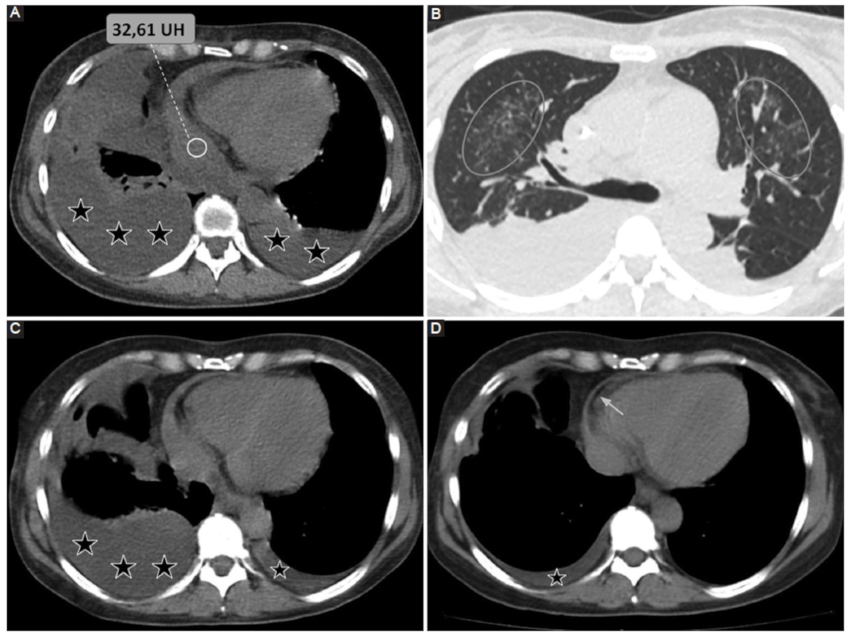

Por su parte, el análisis de la densidad del DP resulta una herramienta complementaria útil y accesible. Se ha estudiado la composición del DP por medio de la medición de densidades tomográficas y su correlación con los datos del análisis bioquímico. En este sentido, una densidad promedio similar a la del líquido es indicativa de trasudado, mientras que valores mayores a 20 UH se vinculan con exudados y mayores a 50 UH con contenido hemático con alta especificidad (Fig. 1) (3,7.

Entidad definida por la presencia de aire contenido entre ambas hojas del pericardio. Si bien puede darse de forma idiopática, las causas más frecuentes son postraumática y posquirúrgica (Figs. 3 y 4), secundaria a patología de órganos adyacentes (tubo digestivo o vía aérea) o afecciones del pericardio por gérmenes productores de gas9.

La gravedad del cuadro viene determinada por la posibilidad de desarrollarse un neumopericardio a tensión, el cual genera un síndrome de taponamiento cardiaco con descompensación hemodinámica y requiriendo descompresión de urgencia9.

La TCMC pone en evidencia la presencia de aire contenido entre las hojas del pericardio, aunque en situaciones de urgencia el diagnóstico de taponamiento cardiaco suele ser clínico6.

Compromiso del pericardio por patología tumoral

Los métodos por imágenes revelan la presencia de compromiso pericárdico, así como signos de afectación extrapericárdica (parénquima pulmonar, estructuras mediastinales y óseas). Los hallazgos por TCMC presentan una amplia variabilidad de presentación, entre los que se menciona:

DP, generalmente del tipo exudado.

Engrosamiento irregular del pericardio.

Lesiones nodulares y masas pericárdicas.

Adenomegalias mediastinales (definiéndose como ganglios linfáticos mayores a 10 mm en su eje corto).

Hemopericardio

Iatrogénico: en este grupo se engloban el hemopericardio secundario a procedimientos cardiacos invasivos tales como la intervención coronaria percutánea o la colocación de marcapasos (Fig. 9); o como consecuencia de una cirugía cardiovascular (Fig. 10).

Trauma torácico: fuerzas de alta energía que llevan a la presencia de hemopericardio, ruptura pericárdica, taponamiento cardiaco y/o herniación.

Síndrome aórtico agudo: en este contexto, el hemopericardio ocurre con una frecuencia estimada de entre un 17-45%, hecho que contraindica la pericardiocentesis y representa una emergencia clínica (Fig. 11) (6.

Los métodos por imágenes están indicados para la valoración de cuantía y severidad con un nivel de evidencia B clase 1 según las guías vigentes6. Según la serie de Rifkin et al. (3, la TCMC, entre otras cosas, permite identificar la presencia de hemopericardio ante una densidad promedio mayor a 30 UH con una sensibilidad cercana al 100%.